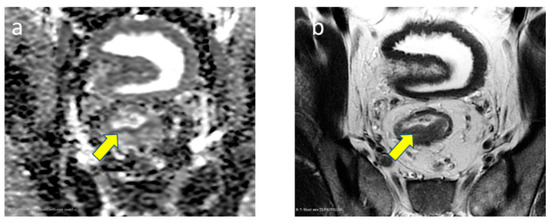

3.2.5. EMVI Status